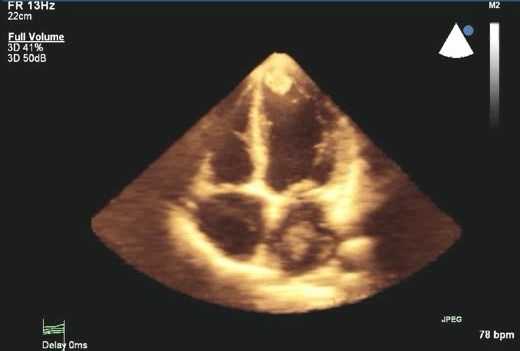

Проведение двухмерной ЭхоКГ дает важную анатомическую информацию.

Двухмерная эхокардиография может выявить структурные аномалии протеза, такие как фистулу, вегетации, тромб, или дегенерацию ткани протеза. Однако ее чувствительность к сердечной дисфункции протеза затрудняется трудностью визуализации структур вокруг и позади сердечного протеза. Эхо отражение от протезного материала, затухание ультразвукового луча, и несколько других ультразвуковых артефактов от протеза могут вызвать трудности в толковании. Обычно, на эхокардиографии легче изучить изображения биологического протеза, чем механического. Для выявления структурных аномалий, связанных с протезом, важно понимать характеристики протеза и хирургический метод, который был использован.